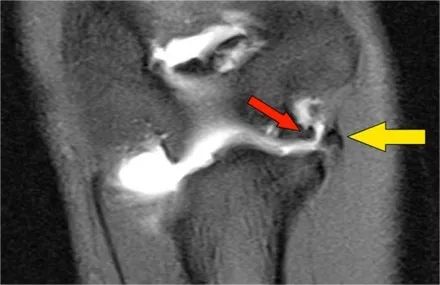

肘关节脱位这是一个患者肘部的侧位片。X光片显示关节积液(红色箭头)和冠状突骨折(黄色箭头)。

下面是MR● 冠状图片:侧副韧带完全剥离(黄色箭头)。桡骨头是半脱位的。由于骨折引起的冠突骨髓水肿(红色箭头)。● 矢状面观:桡骨头稍后有点半脱位(黄色箭头)。大量积液和囊后破裂。● 由于冠状突的撞击(红色箭头)导致的头颅后侧的挫伤。所有这些迹象都是后脱位的结果。